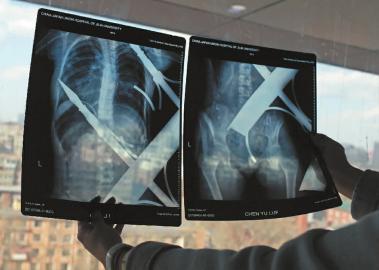

X光片顯示一根鋼筋將小女孩的右側(cè)肩膀刺穿,另外一根則從后背腰部以上靠近脊椎的地方穿入 白石 攝

在急診室的病床上,李紅旭看到了小雨。“她掛著吊瓶,意識(shí)比較清醒?!边M(jìn)一步觀察,李紅旭一時(shí)說(shuō)不出話來(lái)———一根鋼筋穿透小雨右側(cè)肩膀,另一根則從后背腰部以上靠近脊椎的地方穿入,從小雨左肩部分穿了出來(lái)。兩根鋼筋由兩根角鐵連接,距離事發(fā),小雨背著這片鐵柵欄已經(jīng)近7個(gè)小時(shí)了。